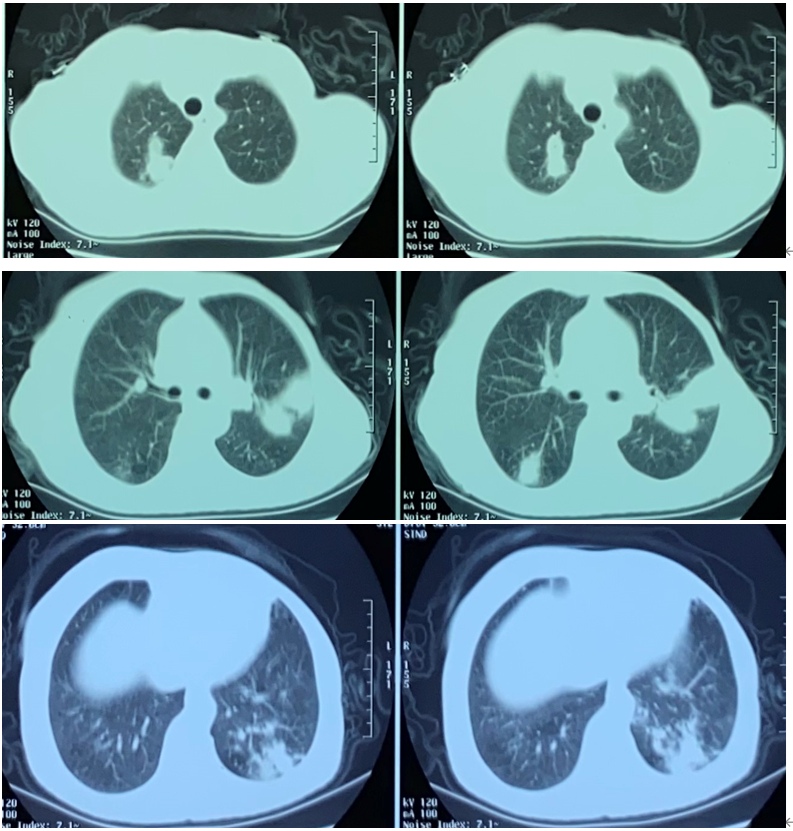

肉芽肿性多血管炎(肺部病变)

图片尺寸1146x749